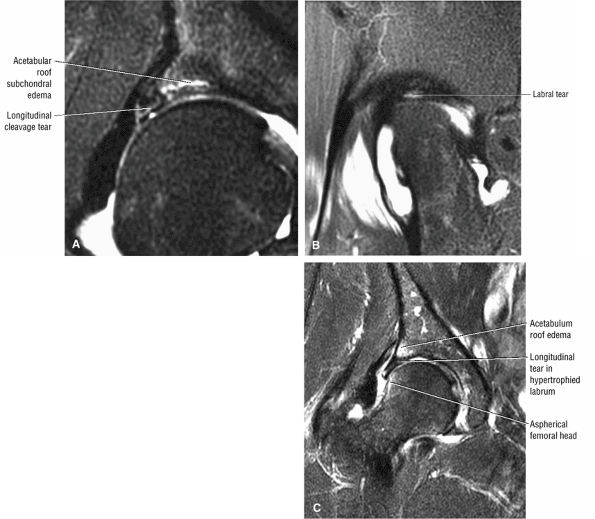

In DDH the labrum may be hypertrophic and associated with a femoral head chondral crease.

An enlarged or hypertrophied labrum may occur in patients with mild DDH.17 We have observed a femoral head chondral crease (Fig. 3.66) in these patients, creating a demarcation trough medial to a femoral head bump immediately proximal to the physeal scar. Patients who demonstrate femoroacetabular impingement (or lateral acetabular rim syndrome in DDH) also have direct impingement between the lateral acetabular labrum and the femoral head.

patient. Unfortunately, the hypertrophic labrum is exposed to greater joint reaction forces and is at an increased risk for symptomatic tearing. The acetabular labrum may also become inverted, entrapped, and subsequently torn. Direct contact between the hypertrophied labrum and the femoral head chondral surface may produce a chondral crease demarcating a femoral head bump formed proximal to the physeal scar. This finding is associated with a lateral acetabular rim or the DDH equivalent of FAI. Anterior coronal MR images evaluated at the level of the anteriormost portion of the femoral head are sensitive to asymmetry in the slope of the acetabulum. The anterior acetabular roof should maintain a relatively horizontal slope and not open up or deviate from the horizontal plane.

FIGURE 3.101 ● (A) DDH associated with longitudinal tearing of a hypertrophied labrum. The shallow slope of the acetabulum is demonstrated. The transverse angle of the osseous acetabular rim affects the degree of lateral coverage and is increased in adult DDH. (B) The normal angle of 40° is shown in contrast to (A).